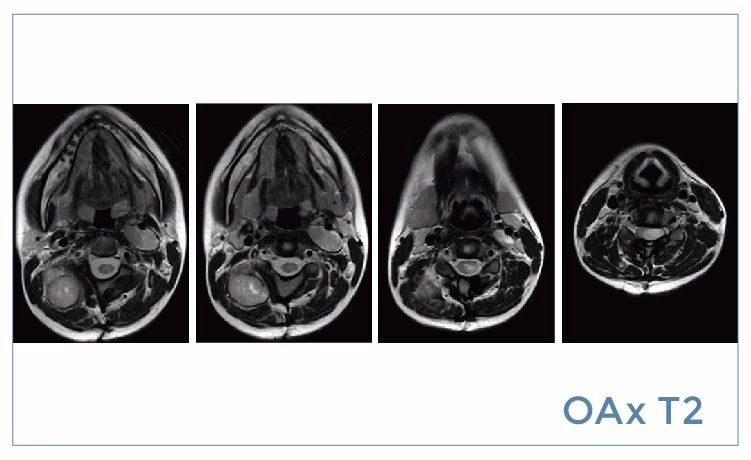

【朗润影像档案】20190816磁共振影像病例结果讨论